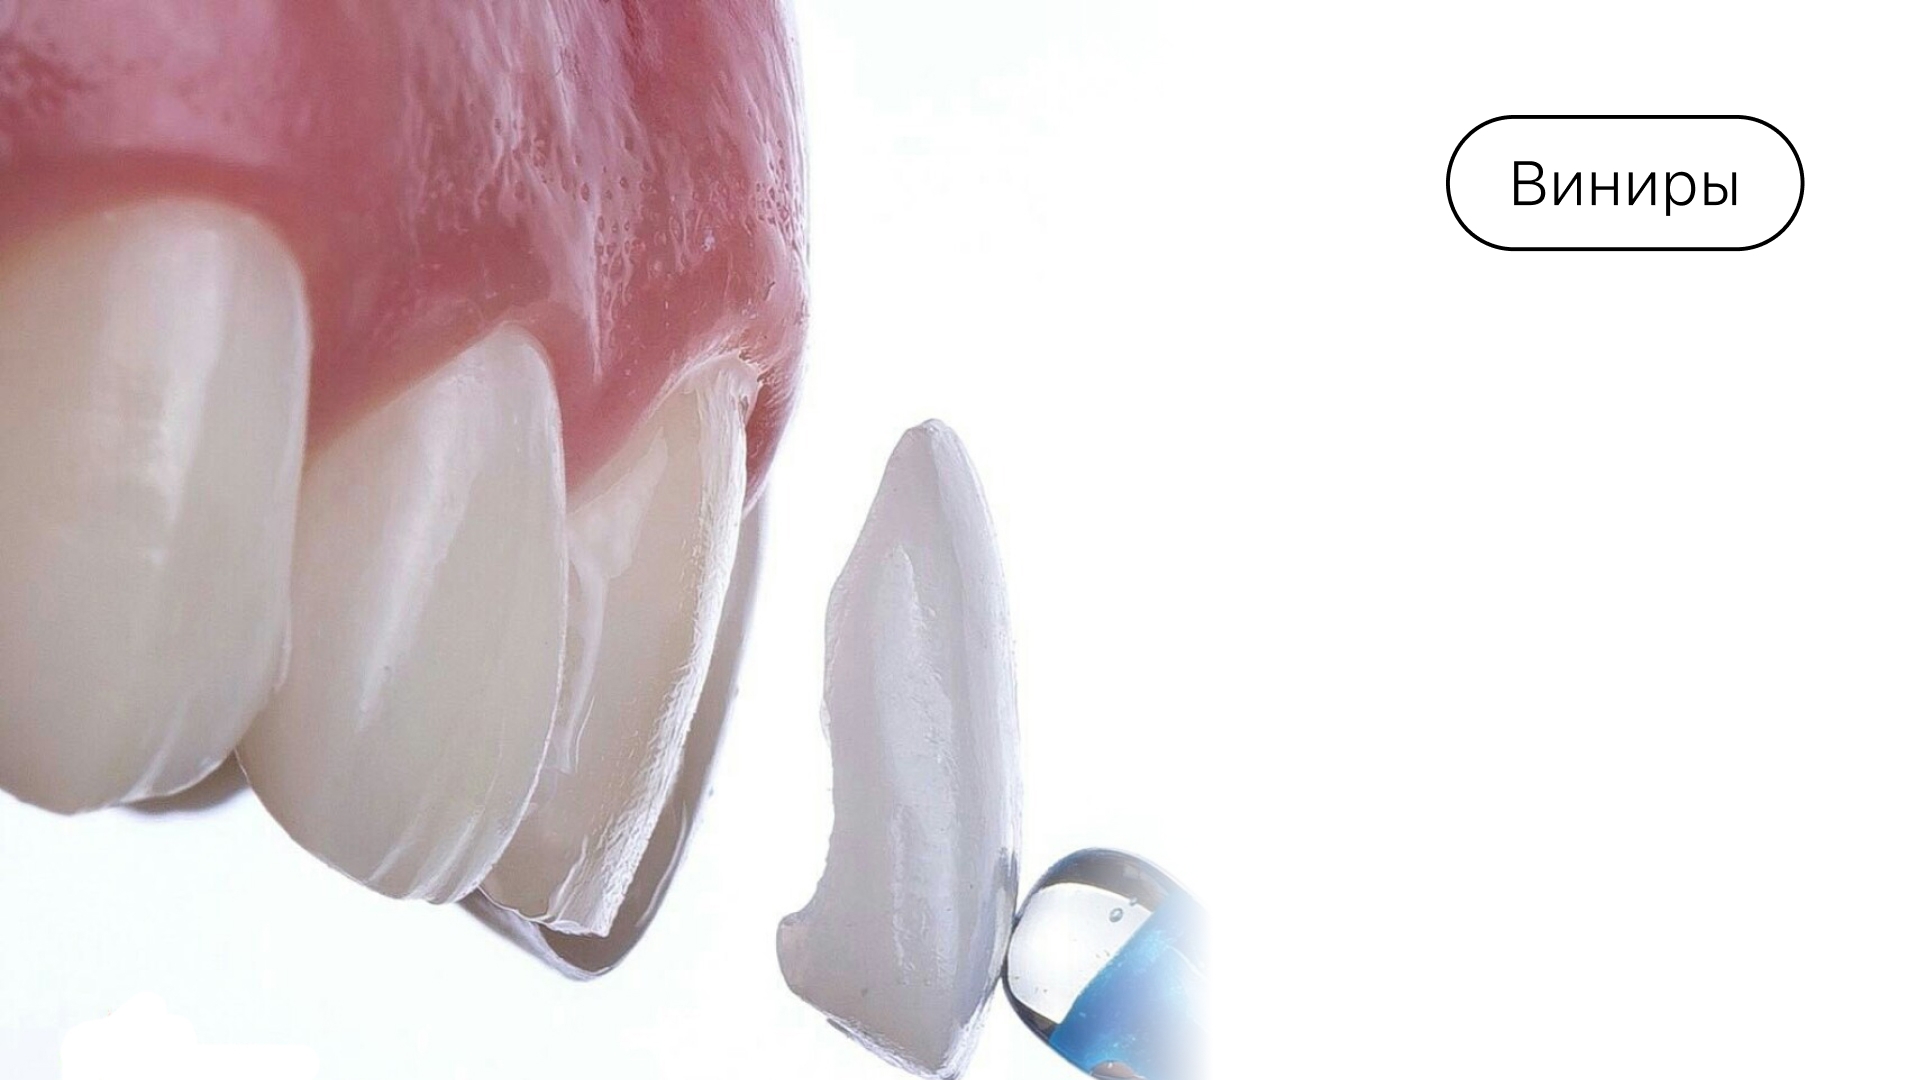

Виниры

Взрослым пациентам некоторые врачи рекомендуют для косметического выравнивания виниры (при незначительных дефектах). Тонкие керамические накладки устанавливают на поверхность резцов, что позволяет улучшить улыбку. Виниры носят всю жизнь, однако спустя 10-15 лет может потребоваться их замена.

Cтоит помнить, что возможность их применения зависит от степени выраженности мезиального прикуса. Окончательное решение о возможности применения данной методики принимает врач-ортопед.